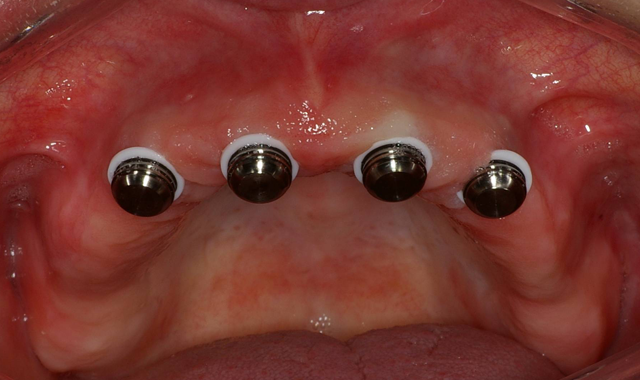

Palpation and radiographic examination revealed a moderately sized maxillary ridge in the anterior portion (Fig. 1) that would only provide sufficient height and width for small diameter implants. However, in the posterior sections there was insufficient bone due to the pneumatization of the sinus cavities. All risks, benefits and alternatives regarding various treatments were discussed with the patient. After a thorough discussion of treatment options, the patient decided she would like to have four dental implants placed in her premaxilla region that would retain a metal-reinforced, palate-free maxillary denture.

Fig. 1 Fig. 2

Using the CS 8100 3D (Carestream Dental), a CBCT scan was taken to accurately treatment plan this case to make certain that no complications would arise from the conservative non-flap approach of placing dental implants. Using 3DDX virtual assistance to precisely plan the placement of four 3.25-by-12 mm EngageTM (OCO Biomedical) dental implants in the anterior portion of the pre-maxilla area, a treatment plan was devised (Fig. 2).